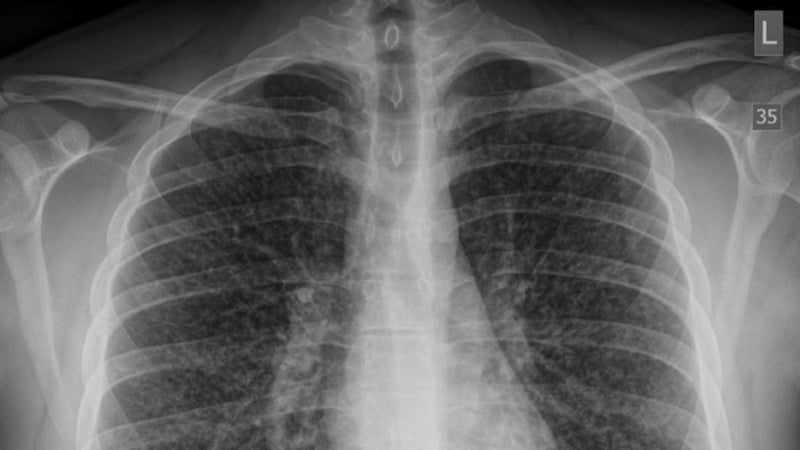

Médicos detectan el primer caso de una enfermedad pulmonar potencialmente mortal relacionada con el vapeo